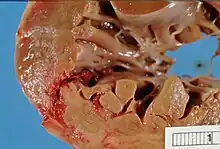

Post-myocardial complications occur after a period of ischemia, these changes can be seen in gross tissue changes and microscopic changes.[1] Necrosis begins after 20 minutes of an infarction. Under 4 hours of ischemia, there are no gross or microscopic changes noted.[2] From 4-24 hours coagulative necrosis begins to be seen, which is characterized by the removal of dead cardiomyocytes through heterolysis and the nucleus through karyorrhexis, karyolysis, and pyknosis.[3] On gross examination, coagulative necrosis shows darkened discoloration of the infarcted tissue. The most common complication during this period is arrhythmias. Day 1-7 is marked by the inflammatory phase. Days 1-3 are marked by “acute inflammation”, in which neutrophils infiltrate the ischemic tissue. A major complication during this period is fibrinous pericarditis, particularly in transmural ventricular wall damage (an infarct that impacted all 3 layers of the heart, the epicardium, myocardium, and endocardium). This leads to inflammation, such as swelling, leading to rubbing of the heart on the pericardium. Day 4 through 7 are marked by “chronic inflammation”, on histology macrophages will be seen infiltrating the tissue. The role of these macrophages is the removal of necrotic myocytes. However, these cells are directly involved in the weakening of the tissue, leading to complications such as a ventricular free wall rupture, intraventricular septum rupture, or a papillary muscle rupture. At a gross anatomical level, this staged is marked by a yellow pallor. Weeks 1-3 are marked on histology by abundant capillaries, and fibroblast infiltration. Fibroblasts start replacing the lost cardiomyocytes with collagen type 1 and leads to the granulation of tissue. After several weeks fibrosis occurs and heavy collagen formation. Collagen is not as strong or compliant as the myocardium that it replaced, this instability could lead to a ventricular aneurysm, and the stasis of blood in an aneurysm can lead to a mural thrombus. A rarer complication that also occurs during this time is Dressler's syndrome and is thought to have autoimmune origins.[4]

Myocardial rupture

Myocardial rupture is most common three to seven days after myocardial infarction, commonly of small degree, but may occur one day to three weeks later. In the modern era of early revascularization and intensive pharmacotherapy as treatment for MI, the incidence of myocardial rupture is about 1% of all MIs.[6] This may occur in the free walls of the ventricles, the septum between them, the papillary muscles, or less commonly the atria. Rupture occurs because of increased pressure against the weakened walls of the heart chambers due to heart muscle that cannot pump blood out effectively. The weakness may also lead to ventricular aneurysm, a localized dilation or ballooning of the heart chamber.